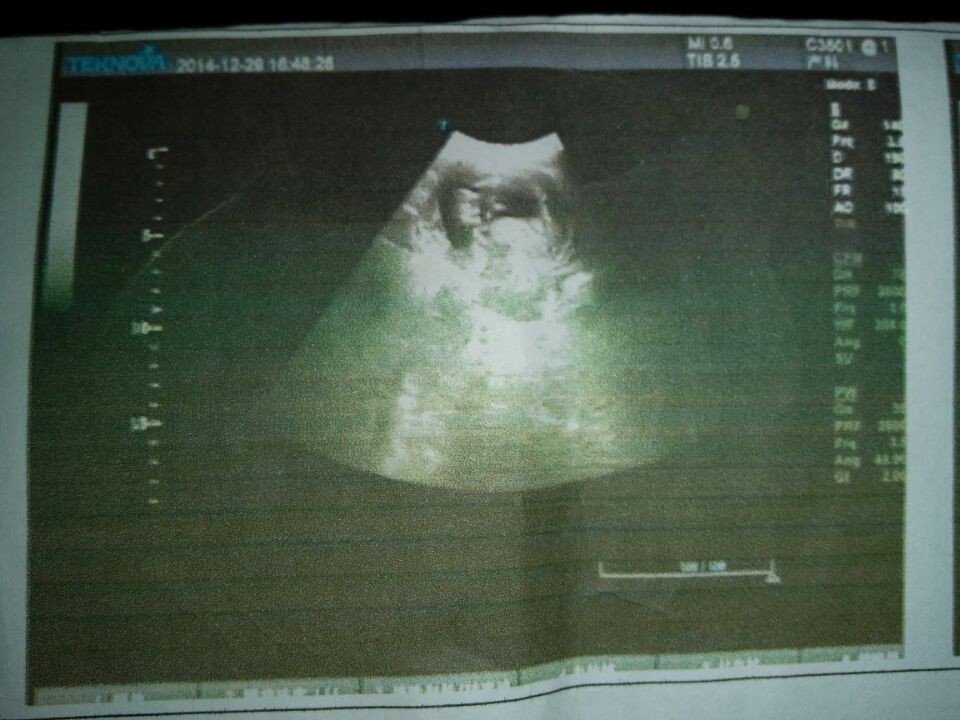

胎盘下缘覆盖宫颈内口,状况堪忧,是做引产安全还是保胎安全,引产有哪些危险? 点击展开 匿名用户 2014-12-30 18:00 为您推荐: 其他回答 您好,前置胎盘容易导致怀孕后大出血的情况,怀孕后期尽量减少活动,延长怀孕时间比较合适的,防止胎盘早剥大出血的情况是比较重要的,必要时住院保胎,出现胎盘早搏,必要时可以提前结束妊娠或清宫处理的。 河北神医喜来乐 2014-12-30 18:19 相关问题 怀孕3个月,胎盘下缘覆盖宫颈内口,是做引产安全还是保胎安全,引产有哪些危险? 我怀孕五个多月了,胎盘位置低,离宫颈口1 9cm,四个多月还出过血,住院保胎过,最近又流点咖啡色的… 昨天突然肚子疼!连夜赶到医院!开了保胎药!医生还说,胎盘低,长在了宫颈口!请问怀孕中期出现这种现状